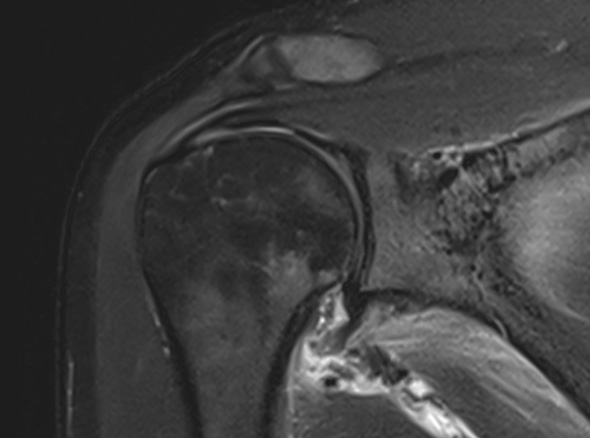

오십견은 어깨를 감싸고 있는 관절 조직인 관절낭에 염증이 발생하면서

유착되어 어깨의 움직임이 제한되고 통증이 유발되는 질환입니다.

오십견은 얼어버린 어깨라고들 부릅니다. 어깨가 움직이는 범위가 점점 줄어들면서

통증을 느끼는 질환입니다. 의학적인 용어로는 동결견, 유착성 관절낭염이라고도 합니다.

내시경을 통하여

유착된 관절낭을 유리화해 줍니다.

이러한 경우

내시경 시술을

고려합니다.